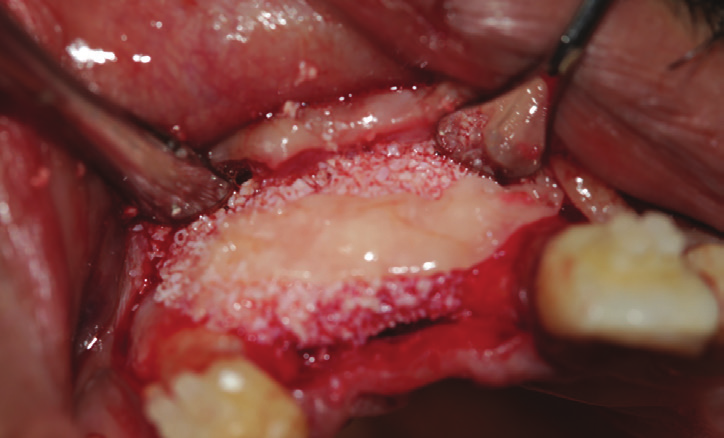

Figure 7: First layer of L-PRF membranes covering the associated xenograft-PRF (sticky bone) obtained that helped stabilizing the graft and insuring hemostasis.

Figure 8: Final layer of coverage formed by L-PRF mem- branes covering the cross-linked collagen membrane.

A PRF collection was done (Fig.5), some were mixed to the xenograft while others converted into autologous fibrin membranes (Fig.6).

A first layer of L-PRF membrane was placed covering the associated PRF xenograft entity, in order to stabilize the graft and insure hemostasis (Fig.7), a second layer covered the cross-linked collagen membrane placed (Fig.8).